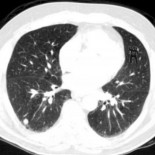

Los radiólogos tampoco vieron el gorila

C&P: Desde hace tres años, explican en NPR, Drew ha convivido con un grupo de radiólogos y ha observado su forma de trabajar. Lo que más le llamaba la atención, relata, es que ellos eran capaces de ver cosas que a él a simple vista se le escapaban, así que se preguntó qué pasaría si sometía a los radiólogos a una prueba de atención.